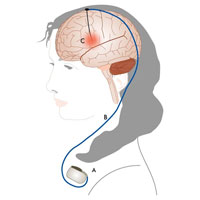

В ситуациях, когда состояние пациента не позволяет проводить стандартные операции, проводятся нейромодулирующие операции, позволяющие, как и стандартная противосудорожная терапия снизить количество и тяжесть приступов, но, к сожалению, не убрать приступы полностью.

К данным методикам относятся:

- Хроническая стимуляция блуждающего нерва (VNS терапия).

- И хроническая стимуляция ядер таламусов (DBS терапия).